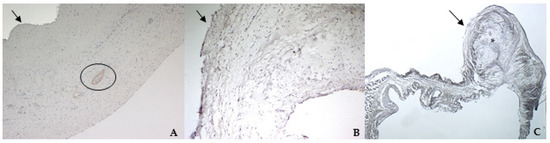

TRPV1 positivity was considered ubiquitous in all samples: it was highlighted in endothelium, endocardium, and spongiosa and fibrosa layers in bovine and both types of canine valves (Figure 8A–C).

The identification of TRPV1 was possible in both bovine and canine VICs using ICC and immunofluorescence. To the best of the authors’ knowledge, this is the first time that this identification is described in valvular interstitial cells. It must be noted that this identification was performed in cells derived from the last third of the leaflet. This specification is necessary since a wide heterogenicity of VICs was described according to the portion of the leaflet from which cells are collected (proximal or other parts) [28,29]. The expression of TRPV1 seemed to be stronger in canine pathological VICs compared to the physiological ones. These data open the possibility to investigate the role of this receptor in different conditions, such as in functional studies in the presence of specific ligands. We also performed IHC to evaluate the entire leaflet; TRPV1 appeared ubiquitous in both healthy and pathological valves. The presence of TRPV1 positivity in myocardial fibers, that normally penetrate into the first proximal portion of the caudal leaflet, and in the wall of small arterioles in the spongiosa layer is in accordance with Guinamard and Hof [21], who described the presence of TRPV1 in specimens of rat and mice myocardium and blood vessel wall. The presence of arterioles in the bovine mitral leaflets is in accordance with previous observations in physiological conditions [30]. Nevertheless, this is the first time that TRPV1 is identified using immunohistochemistry in the arterioles wall of bovine mitral leaflets.

Figure 8. The picture shows positivity to Transient Receptor Potential Vanilloid 1 (TRPV1) in bovine (A) (magnification: 5×) and healthy (B) (magnification: 10×) and pathological (C) (magnification: 20×) canine mitral leaflets. Black arrows indicate the atrial aspect, while the yellow arrow indicates a strong positivity in myocardial fibers that normally penetrate into the proximal portion of the caudal leaflet. In (A), the black circle delimitates small arteries in the spongiosa layer.